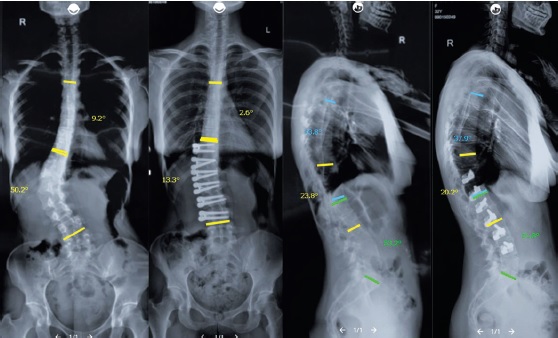

The second group consisted of 32 patients aged 14 to 44 years: 29 women and 3 men. Thoracophrenolumbotomy without rib resection was performed in this group. Two screws with staples (buttress plates) were inserted into the vertebral bodies, and correction was performed using two cords (Fig. 2). Zimmer Dynesis system was used in this group.

Fig. 2. X-rays of a 32-year-old patient before and 2 years after posterior correction and T11-L4 fixation. No loss of correction was observed. No signs of bone block formation were noted